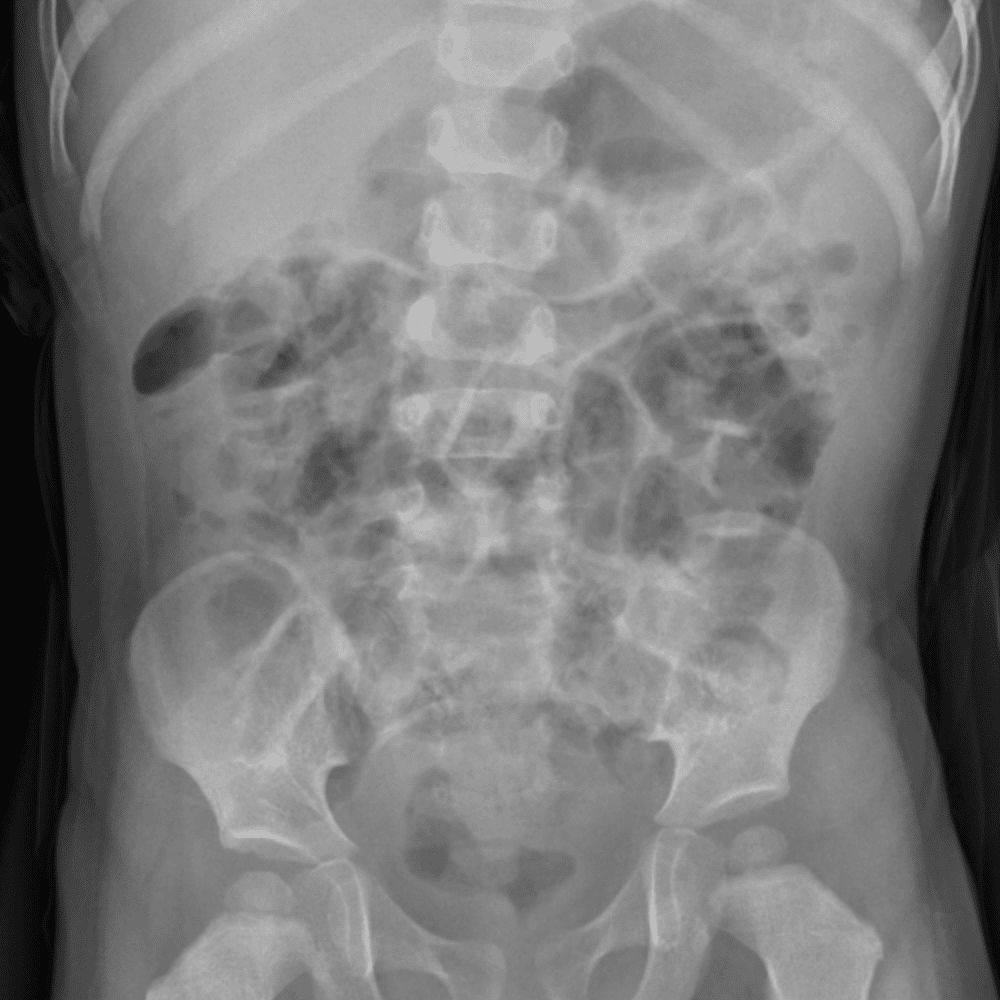

Peds Abdomen

Practice

Simulates call by including subtle or difficult cases and some normals.

30 cases